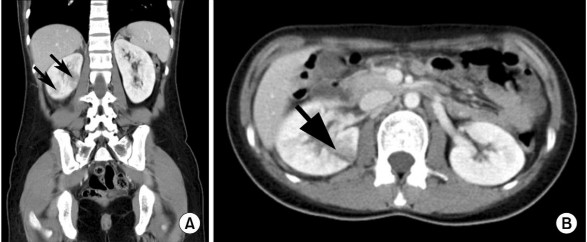

Tiêu chuẩn chẩn đoán VTBT cấp tính tắc nghẽn do sỏi niệu quản trên chụp cắt lớp vi tính là sau khi tiêm thuốc cản quang vào tĩnh mạch ở thì nhu mô thận có hình ảnh: vùng giảm tỷ trọng ở vỏ thận hình chêm, dạng đường thẳng hoặc mảng. Vỏ thận ngấm thuốc hình tia có thể gợi ý VTBT cấp tính [205].

Hình 1.6. Hình ảnh VTBT cấp tính trên phim chụp cắt lớp vi tính ở thì nhu mô sau khi tiêm thuốc cản quang

(Nguồn: Yoo J.M., 2010) [205]